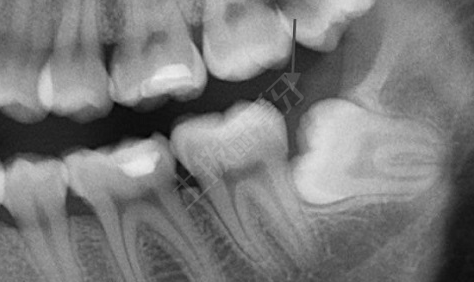

智齒不正常萌出

這一種類(lèi)型的牙齒,通常埋在牙槽骨的里面,后期繼續(xù)生長(zhǎng)會(huì)擠到前面大牙,若沒(méi)有拔除智齒會(huì)容易造成牙齒移位導(dǎo)致效果反彈。但是如果你智齒阻生或者頻繁發(fā)炎,不管有沒(méi)有做牙齒矯正,只要智齒給你造成了困擾,也是需要拔除的。